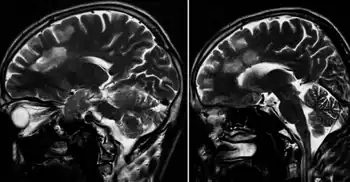

Lesions under MRI are distinctive due to their natural concentric shape.

Lesions under MRI

Baló's concentric sclerosis lesions can be distinguished from normal lesions on MRI showing alternating hypointense and hyperintense layers[25]

Baló's concentric lesions can be viewed using the myelin water imaging techniques. This is a special MRI sequence that shows the myelin's percentage of water content.[26]

Pattern III lesions, including Baló lesions, have a specific initiation pattern under MRI (MRILIP) consisting in showing Gadolinium enhancement before FLAIR MRI appearance.[27]

Under 7-Tesla MRI Ball lesions show a center vein, like in MS.[28]